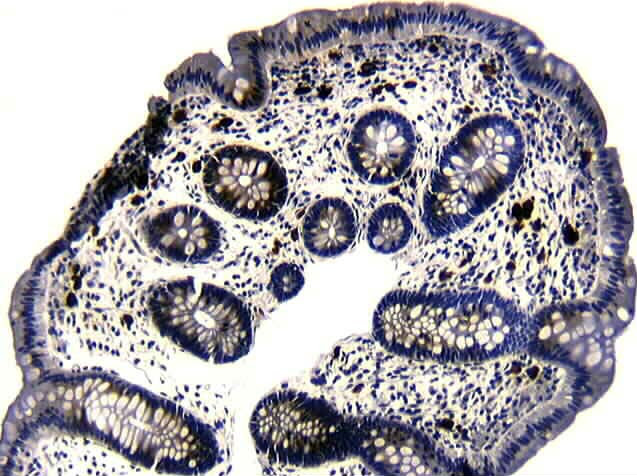

Mesothelioma pathology mesothelioma signs. Domestic > mesothelioma signs > mesothelioma analysis > mesothelioma pathology. Peritoneal mesothelioma; mesothelioma pathology. Pathology outlines mesothelioma general. Malignant mesothelioma arises from mesothelial lining of pleura, peritoneum, pericardium and tunica vaginalis pleural mesothelioma is the maximum not unusual of those. National mesothelioma lawyers nemeroff regulation company. Talk your case with a caring and informed mesothelioma lawyer from the nemeroff law firm as soon as viable. Homepage flint regulation firm mesothelioma lawyers. Cash is to be had for mesothelioma & asbestos lung most cancers victims. Agencies who had been, and are nevertheless, liable for asbestos claims have positioned aside over $30 billion into. Carcinogen wikipedia. A carcinogen is any substance, radionuclide, or radiation that promotes carcinogenesis, the formation of most cancers. This may be because of the capability to damage the genome.

Gene 7157 country wide center for biotechnology records. This gene encodes a tumor suppressor protein containing transcriptional activation, dna binding, and oligomerization domains. The encoded protein responds to numerous. 키다리방방 초지점 키즈카페 kidaribangbang.Kr. 1. 넓은 방방시설과 파티룸과 단체예약가능합니다. 2. 인근지역 초지동,호수동,선부동,사동 키즈카페). Full textual content of "new" net archive. Seek metadata seek full text of books search television captions seek archived internet websites superior search. New orleans damage, coincidence law firm asbestos. New orleans non-public harm lawyers with the gertler regulation company help area residents pursuing complaints for vehicle accidents,mesothelioma,mind injury,medical. Pathology outlines peritoneum, omentum & mesentery. This internet site is meant for pathologists and laboratory personnel, who remember that medical records is imperfect and have to be interpreted using affordable. Pathology of malignant pleural mesothelioma uptodate. Mesothelioma is a malignant tumor that arises from the mesothelial surfaces of the pleural and peritoneal cavities, the tunica vaginalis, or the pericardium. Eighty.

Mesothelioma pathology outlines. This pathology define for mesothelioma is centered on providing you with targeted data approximately the disorder. The once a year prevalence of mesothelioma. Thornton law firm massachusetts mesothelioma legal professionals. Additionally strive. Gene 7157 national center for biotechnology information. This gene encodes a tumor suppressor protein containing transcriptional activation, dna binding, and oligomerization domains. The encoded protein responds to numerous. Mesothelioma lawyer shrader & buddies l.L.P.. Also strive. Pleura benign multicystic mesothelioma pathology outlines. Case reviews ===== sixteen year antique with multicystic peritoneal mesothelioma (am j case rep 2012;13262).